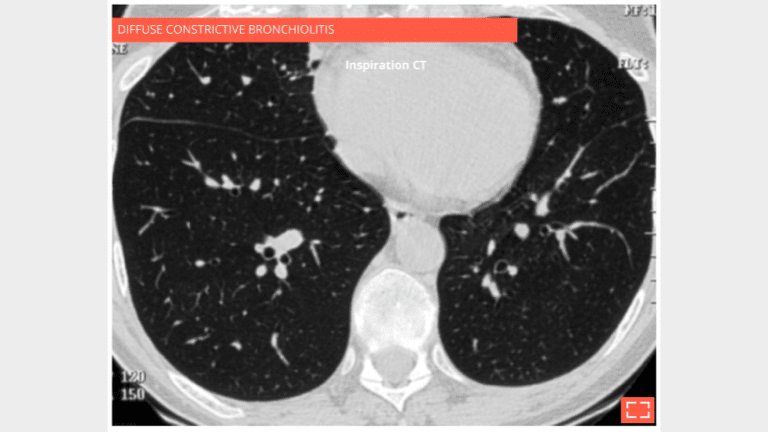

Diffuse constrictive bronchiolitis in a bone marrow transplant patient with shortness of breath and obstructive disease.

Inspiratory CT: the lung is over inflated, hypodense overall, but homogeneous.